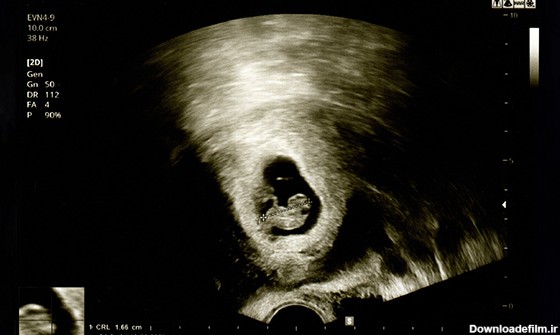

اندازه جنین یک ماهه کوچکتر از یک دانه برنج است! اما در ماه اول بارداری خصوصیتهای ژنتیکی شکل میگیرد. آیا جنین یک ماهه جفت دارد؟ | عکس جنین یک ماهه در شکم مادر

در این مقاله در مورد تکامل اصلی جنین در هفته می خوانید و اندازه جنین مشخص میشود